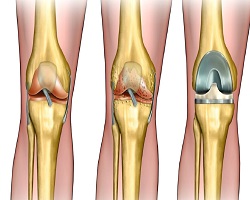

ГОНАРТРОЗА

Гонартроза представља хронично дегенеративно обољење коленског зглоба које се карактерише постепеним пропадањем зглобне хрскавице, променама на субхондралној кости и појавом бола и смањене покретљивости. Ово обољење је један од најчешћих узрока инвалидитета код старије популације, али се све чешће јавља и код млађих особа услед гојазности, повреда и повећаног физичког оптерећења. Циљ овог рада је да се прикажу узроци, клиничка слика, дијагностика и терапијске могућности гонартрозе.